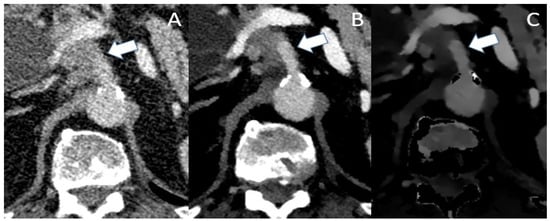

A patient presenting with abdominal pain who received a single-phase protocol is shown in Figure 1, in which VMI and ID show a more clearly visible and well-demarcated lesion of the pancreatic corpus, which was later confirmed to be PDAC. Currently there are no studies directly comparing the benefits of SDCT to MRI in the detection of small or hypoattenuating lesions. However, several studies indicate good diagnostic performance of MRI in lesions <2 cm, with sensitivities ranging from 90 to 100% [45,46]. In particular, DWI has a good diagnostic performance with a sensitivity of 92–96% and specificity of 97–99% [47,48]; however, DWI has its limitations in differentiating mass-forming pancreatitis from PDAC, its similar ADC values [48]. With spectral CT, VMI and IDM can be used to improve the sensitivity and the specificity for the differentiation of mass-forming pancreatitis from PDAC [49].

Figure 1. (A) The conventional CT image shows an ill-defined, moderately hypoattenuating mass of the pancreatic corpus in the portal venous phase (marked with the arrow). In VMI (B) and iodine density maps (C), the hypoattenuating tumor is more clearly visible with sharp demarcation to the adjacent pancreatic parenchyma.